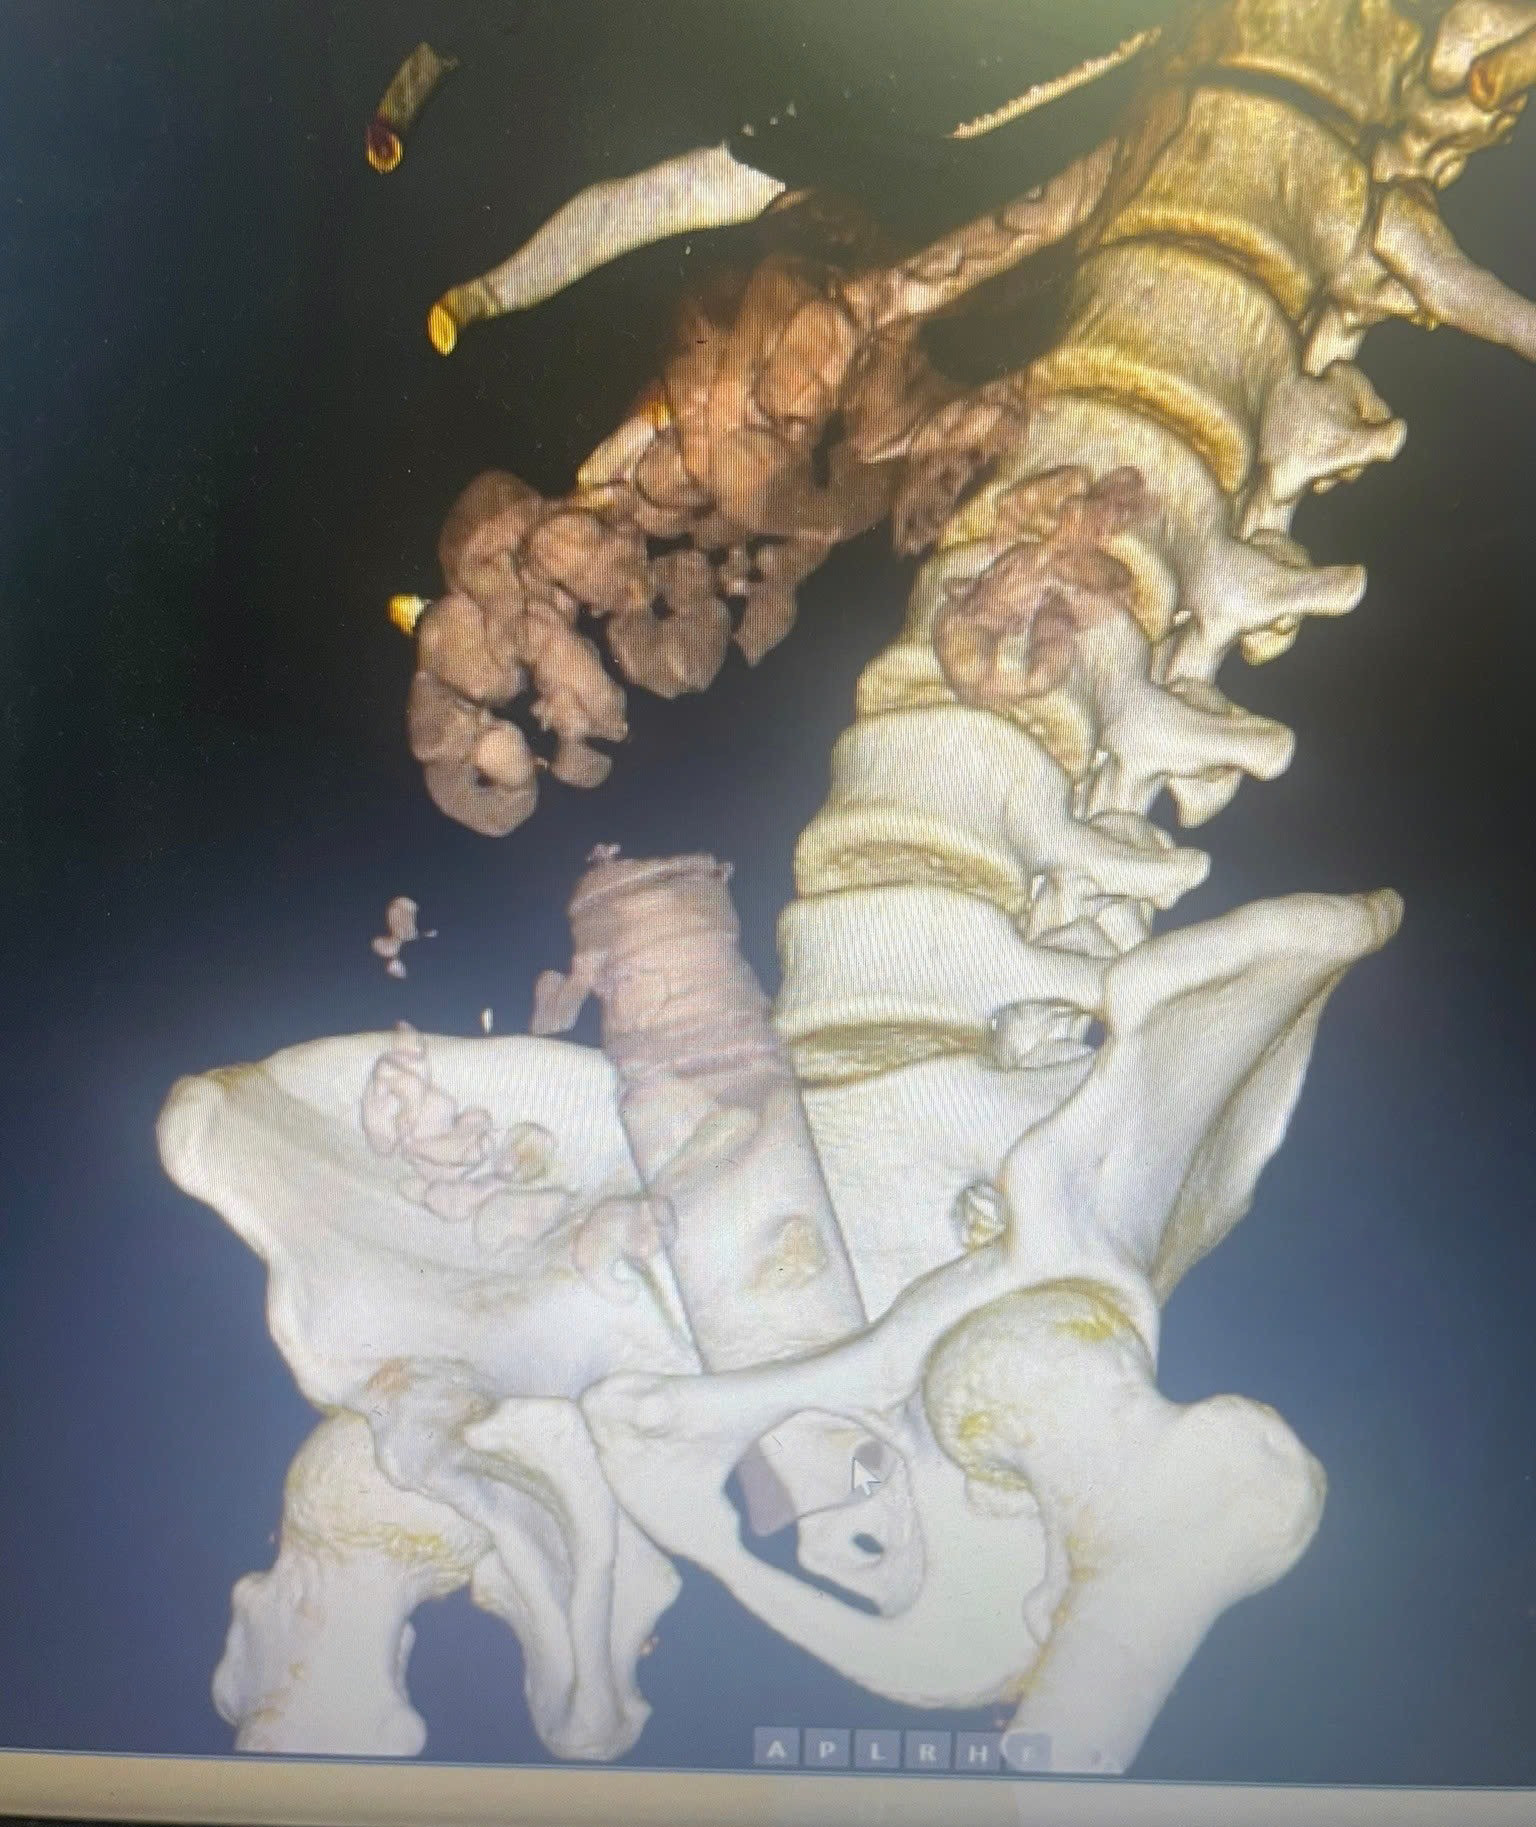

Hình ảnh dị vật trên phim chụp. Ảnh: BSCC.

Bệnh viện đã tiến hành chiếu chụp cắt lớp vi tính đánh giá vị trí dị vật và nội soi đại trực tràng để gắp dị vật. Qua phim chụp, bác sĩ cũng hoảng vì dị vât quá lớn chèn vào đường tiêu hóa.